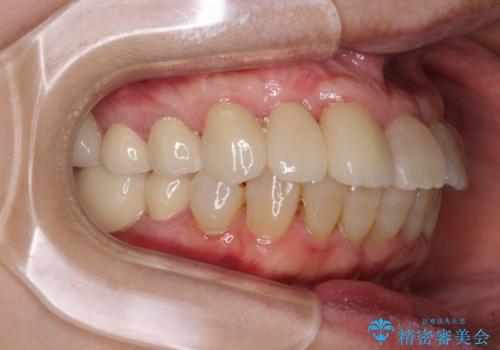

- 歯の欠損や歯肉からの出血などを気にして来院された患者様です。

診査の結果、歯周病であることが分かり、抜歯が必要な歯も見受けられました。

骨造成やインプラント、歯周外科、歯肉移植、矯正など、多くの処置を組み合わせて治療を行うこととしました。

数多くの外科処置を行ったため、治療期間は長期間となりました。

一方、外科処置をしっかりと行ったことで、歯周病の状態は改善され、安定した状態にしあげることができました。